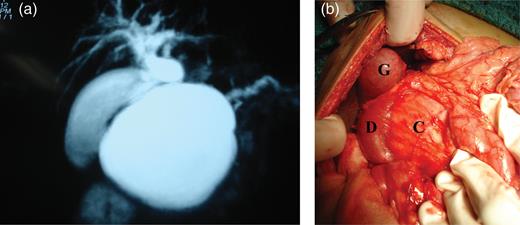

An 8-year-old boy presented to our hospital with jaundice and intermittent pain in the abdomen since last 1 year after a trivial blunt abdominal trauma sustained while at play. Jaundice was insidious and was gradually progressive and was associated with upper central abdominal pain which was intermittent. Pain was not radiating and of no specific character. There was no history of fever, bowel or urinary complaints. Past history was unremarkable. The patient was icteric and abdominal examination revealed a solitary mass in the upper mid-abdomen which was oval in shape and measuring 15 cm vertically and 10 cm horizontally. The upper margin was imperceptible from the inferior liver edge. It was not tender and not mobile. The liver edge was palpable 3 cm below the right costal margin. A clinical diagnosis of choledochal cyst was made and further investigated. Hemogram was within the normal limits. Liver function tests showed: total bilirubin was 2.8 mg/dl (direct 2.4 mg/dl), normal enzymes and raised alkaline phosphate (3881 U/l). Sonography was suggestive of choledochal cyst with hepatomegaly. Magnetic Resonance Cholangiopancreatography (MRCP) gave a picture of a type 1 choledochal cyst (Fig. 1a).

(a) MRCP with 2D-reconstruction demonstrating features indicating a type 1 choledochal cyst, (b) intra-operative showing gallbladder (G), duodenum (D) stretched and compressed with widened C loop of duodenum and the pseudocyst (C) within.

The patient was operated and the intra-operative findings (Fig. 1b) were of a large pseudocyst of pancreas arising predominantly from the head and body of the pancreas. The ‘C loop’ of the duodenum was splayed and stomach was pushed up anteriorly. Gall bladder and the portal anatomy were normal. The liver was enlarged and surface had fine nodules. There was no sign of active pancreatitis. An intra-operative cholecystogram was performed that showed unequivocal obstruction of the terminal common bile duct (CBD).